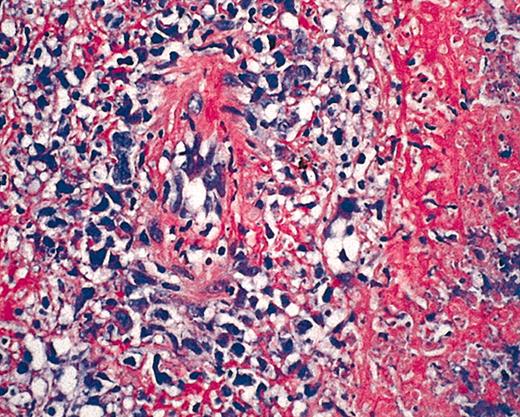

Hematoxylin and eosin (HE) staining of EBV+ B-cell diffuse large-cell lymphoma. Original magnification × 40.

We report a case of acute EBV-associated B-cell diffuse large-cell lymphoma developing shortly after successful treatment of relapsed hairy cell leukemia. In 1998, a 46-year-old patient presented with splenomegaly, leukocytopenia, and thrombocytopenia. The peripheral blood smear demonstrated atypically appearing lymphocytes, resembling hairy cells. The bone marrow biopsy confirmed the diagnosis of hairy cell leukemia by May-Grunwald-Giemsa (MGG) staining, alkaline phosphatase antialkaline phosphatase (APAAP), and immunophenotyping with 85% cells positive for CD103. The patient was treated with continuous intravenous infusions of cladribine (3 mg/m2) for 7 days. His blood counts nearly normalized over the next months, and follow-up bone marrow biopsies confirmed a complete remission. However, in December 2002 a progressive leukocytopenia was detected and in January 2003 a relapse of the hairy cell leukemia was diagnosed by bone marrow biopsy with a 39% infiltration of the bone marrow. Cladribine was initiated again as salvage therapy for 7 consecutive days (3 mg/m2). At 3 weeks after completing the chemotherapy cycle, the patient developed fever, dyspnea, and cough. A computed tomography (CT) scan of the chest revealed typical aspergillosis infiltrates and pleural effusions. The aspergillus antigen in the serum, however, was always negative. Surprisingly, in several blood cultures and in the pleural effusion, high amounts of EBV DNA were detectable by polymerase chain reaction (115 000 genome equivalents/mL in the serum and 950 000 genome equivalents/mL in the pleural effusion). Broad spectrum antibiotics, voriconazole, and cidovir were initiated, leading to clinical improvement and regression of lung infiltrates and pleural effusions. To assess the pneumonia, a control CT scan was performed in April, which revealed regress of infection but also a new mediastinal mass and multiple new cervical lymph nodes (Figure 1A). The biopsy of a cervical lymph node revealed a CD20+ B-cell diffuse large-cell lymphoma that was EBV-associated with expression of latent membrane protein 1 (LMP-1) and EBV nuclear antigen 2 (EBNA-2+) (Figure 2). There was no sign of an infiltration by the hairy cell leukemia in the respective lymph node. At this time the hairy cell leukemia was in complete remission, measured by peripheral blood and bone marrow cytomorphology as well as multiparameter immunophenotyping. In this patient there was no previous history of congenital immunodeficiency. In addition, to exclude an HIV infection an HIV test was performed, which was negative. CD4 counts during this period of time, however, were not measured.As the infection was still not under definitive control and the patient's performance status was reduced, we felt that chemotherapy was not feasible. Therefore, a monotherapy with anti-CD20 monoclonal antibody (rituximab) was initiated at a dose of 375 mg/m2. Currently, the patient is in good general condition and follow-up CT scans revealed a good partial response 3 weeks after 4 applications of rituximab (Figure 1B).